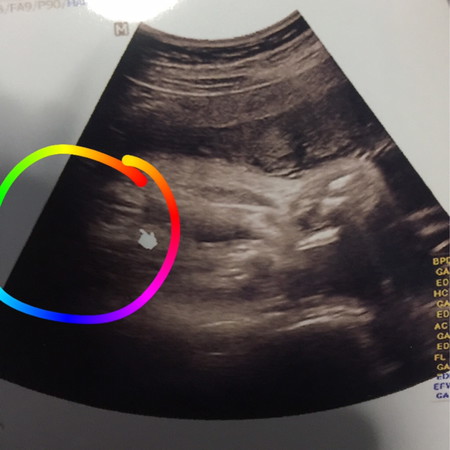

เพศน้อง

แม่ๆเห็นเป็นอะไรคะเห็นตรงกับหมอบอกไหมคะว่าเป็นแฮมเบอร์เกอร์น้อง

ลูกสาวค่ะแม่